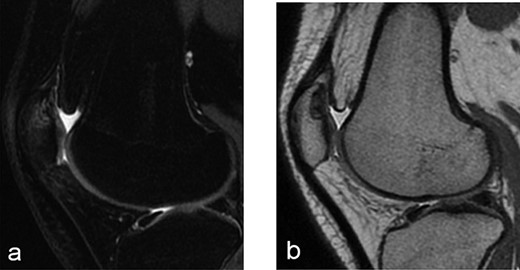

A 14-year-old female dancer presented with increasing right knee pain and functional disability without any trauma. Her pain was retropatellar pain that often radiated medially or laterally from the patella, exacerbated by climbing stairs, running and squatting. She was unable to perform any sports activities. Examination revealed peripatellar tenderness and crepitus, full range of motion and the knee was stable. Radiological examination included both MRI and computed tomography of the knee were performed at the beginning. MRI showed osteochondritis dissecans at the area at the superolateral facet of the patella in the deep subchondral area as shown in Fig. 1. This was appropriately treated conservatively with 6 months of reduced load and protected weight bearing without relief of symptoms. She quit sport activity for 2 years and then another MRI was performed Fig. 2. After 2 years we opted for adipose-derived mesenchymal stromal cells (AD-MSCs) intra-articular therapy according to the procedure described by Tremolada et al. [9]. The patient’s parents were given written information regarding the use of AD-MSCs therapy, including relative risks of this therapy and also relevant treatment alternatives that could otherwise be explored. Postoperative radiological evaluation was performed at 6 months and 12 months after AD-MSCs procedure as shown in Figs. 3 and 4. Postoperative clinical evaluation was performed using IDKC, Lysholm and Tegner scores (Table 1). After surgery, patients began a McConnell program of lateral retinacular stretching, patellar taping and vastus medialis obliquus muscle exercises. The patient was encouraged to swim and cycle to reduce impact loading. Using AD-MSC, she reported a complete relief of pain after 1 year from the procedure. Routine MRI follow-up 2 years later showed evidence of appreciable improvement in cartilage volume and osteochondral architecture at the site of injury. Early MRI T2 mapping at 6 months indicated that the area of cartilage regeneration exhibited high water content suggestive of immature cartilage or fibrocartilage morphology. Later T2 mapping at 18 months after the procedure, indicated progressive maturation of cartilage from deep to superficial layers with more hyaline like cartilage morphology. Limitations of the study are lack of arthroscopic intra-articular visualization and classification of the patella lesion.

Twelve months after MSC treatment in (a) axial and (b) sagital T2-weighted of MRI T2 sequences the OCD in patella showed that area was almost regenerated with good fibrocartilage morphology.